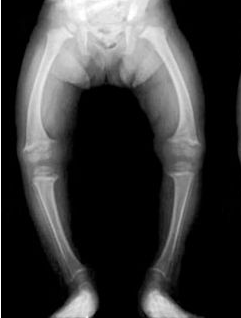

Рахит - патология, которая очень часто диагностируется у детей и возникает при недостатке в организме витамина Д . Родителям, которые заметили, что скелет малыша деформировался, необходимо немедленно обратиться к . . .